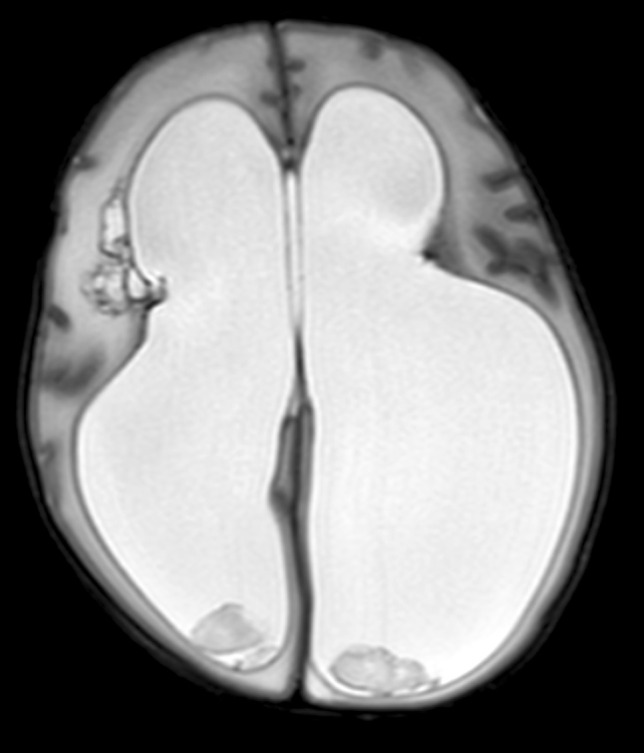

Cranial ultrasound scan demonstrated hydrocephalus secondary to Papile Grade IV intraventricular and intraparenchymal haemorrhage and this was confirmed on subsequent MRI (Fig. 1). An anterior fontanelle tap was performed as part of a workup for cerebrospinal fluid (CSF) diversion, which did not reveal any evidence of infection. She underwent left parietal ventriculoperitoneal (VP) shunt insertion aged 4 weeks (age corrected for prematurity). Three weeks later, she developed non-infectious mechanical shunt dysfunction necessitating re-siting of the ventricular catheter.

Fig. 1.

Axial T2-weighted MRI demonstrating hydrocephalus secondary to Papile Grade IV intraventricular and intraparenchymal haemorrhage